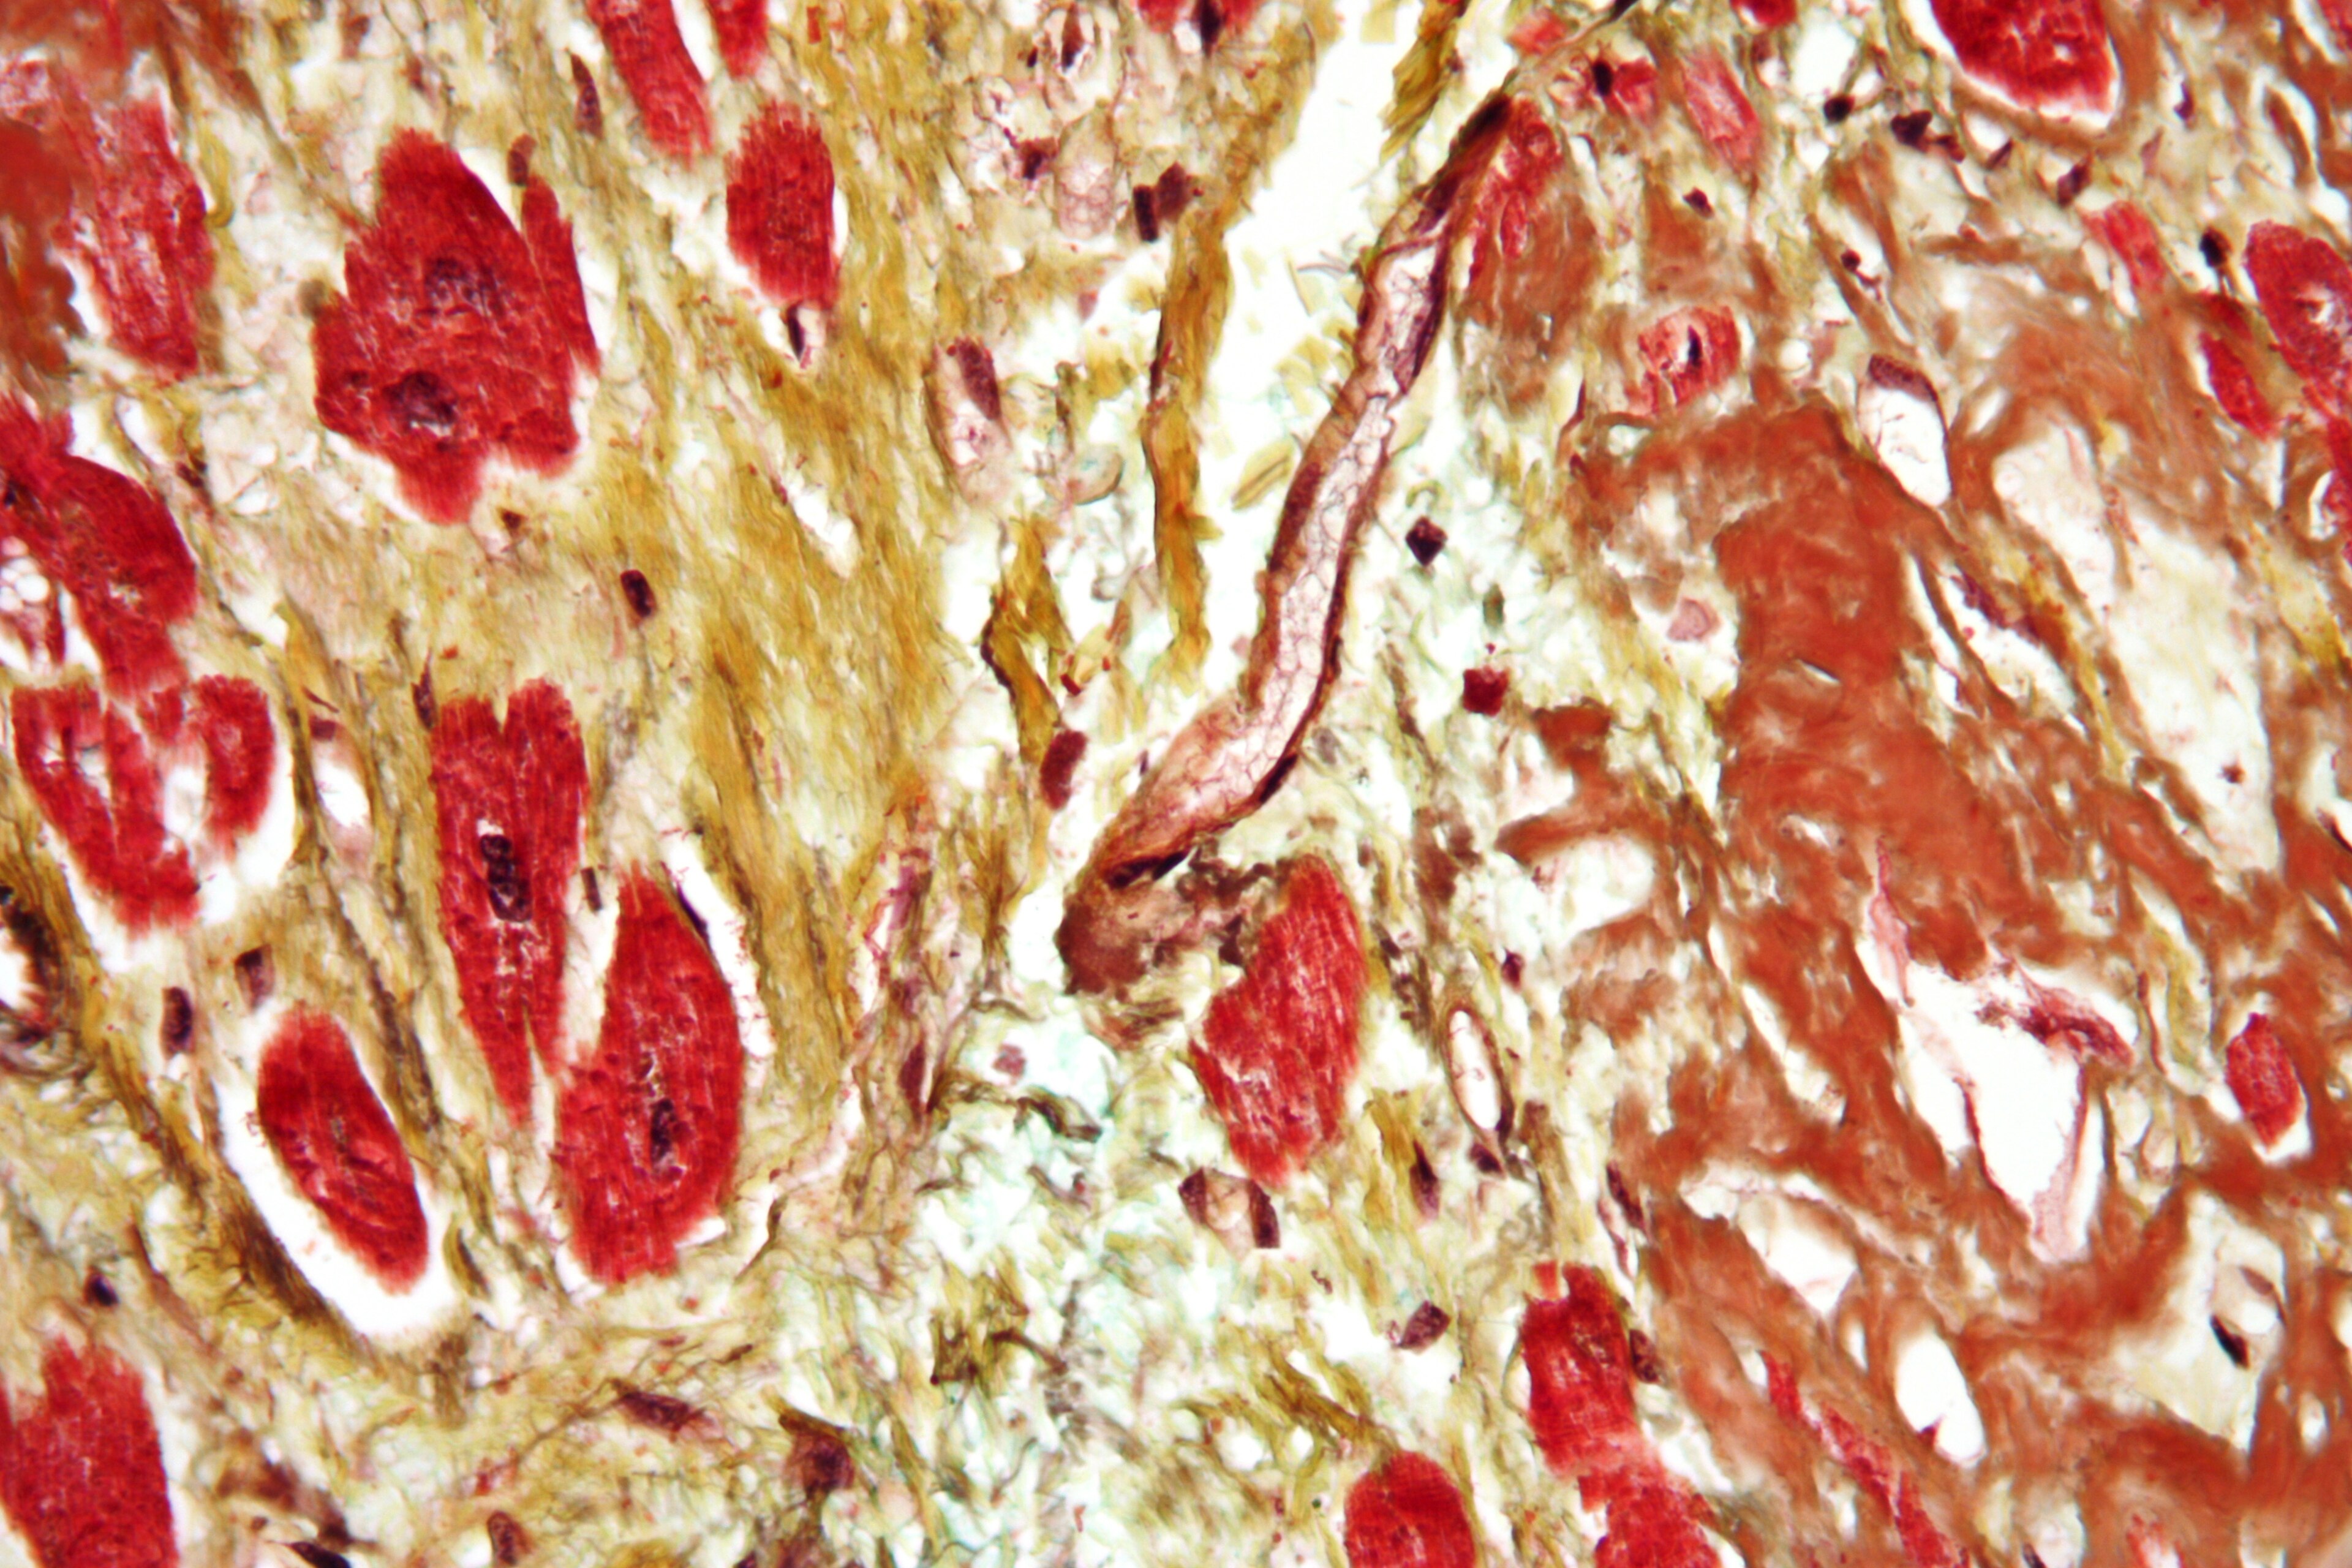

| Mikrograf jantung dengan fibrosis (kuning) dan amiloidosis (coklat). Noda Movat. | |